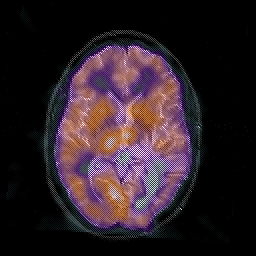

Glioblastoma multiforme overlay -- Slice #28

[Home][Help][Clinical][Tour 1][Tour 2][Tour 3] Slice 28